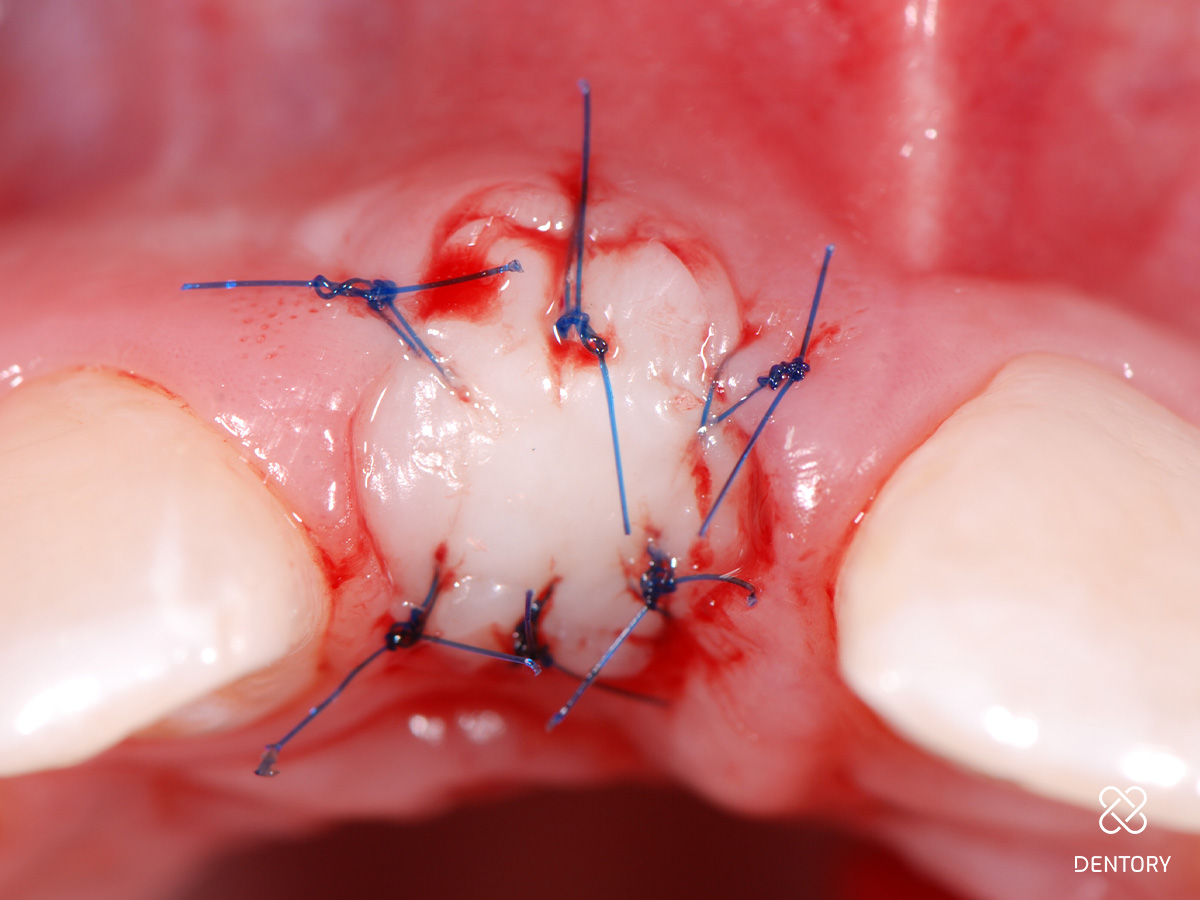

Abbildung 10

Eingenähter Punch vom seitlichen Gaumen: Die Entnahme kann im Prämolaren- oder Tuberbereich erfolgen.